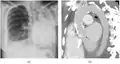

| Fibrothorax on chest x-ray | |

A fibrothorax can typically be diagnosed by taking an appropriate medical history in combination with the use of appropriate imaging techniques such as a plain chest X-ray or CT scan.[3] These imaging techniques can detect fibrothorax and pleural thickening that surround the lungs.[7] The presence of a thickened peel with or without calcification are common features of fibrothorax when imaged.[3] CT scans can more readily differentiate whether pleural thickening is due to extra fat deposition or true pleural thickening than X-rays.[3]

If a fibrothorax is severe, the thickening may restrict the lung on the affected side causing a loss of lung volume.[7] Additionally, the mediastinum may be physically shifted toward the affected side.[3] A reduction in the size of one side of the chest (hemithorax) on an X-ray or CT scan of the chest suggests chronic scarring.[6] Signs of the underlying disease causing the fibrothorax are also occasionally seen on the X-ray.[6] A CT scan may show features similar to those seen on a plain X-ray.[7] Lung function testing typically demonstrates findings consistent with restrictive lung disease.[6]

Extensive left-sided fibrothorax

Chest radiograph displaying inhomogeneous opacification of the left half of the chest that is fibrothorax